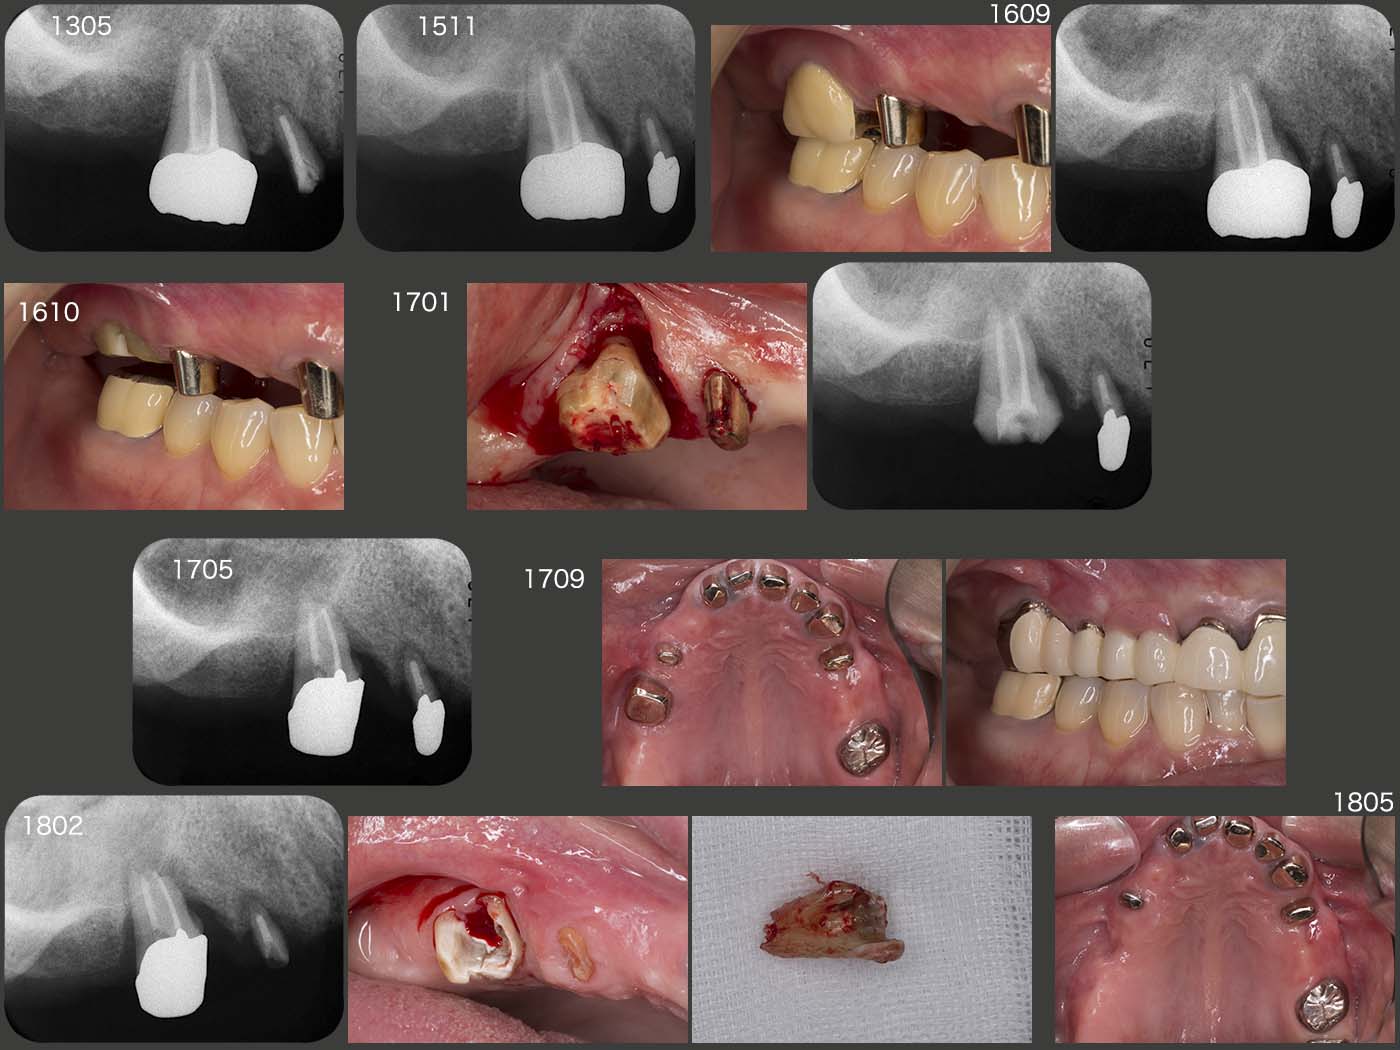

2015年11月,初診終了時の状態.新義歯製作中,咀嚼の中心は右側の上下6であり,これまで,右上6は移植後の歯周ポケットが最大5mmで安定していたが,初診終了時には近心部が7mmまで深化してしまった.

右上6(移植歯)の経過.まずスライド左上は,2013年5月,クラウン装着時の状態であるが,特に問題はない.しかし,15年11月,初診終了時においては,近心に歯周ポケットが7mmあり,デンタルX線写真から近心に透過像が認められる.16年9月の時点では,歯周ポケットが近心で10mmとなったため,クラウンを除去し,力の解放を行った.17年1月に,歯周外科を行い,今度はコーヌス冠を装着して,2次固定効果を期待した.(17年9月装着,歯周ポケットは5mmに回復した.)しかし,18年2月,右上4のコアごと脱離の際,移植歯を精査したところ,頰側歯肉縁下に炎症性吸収が生じ,歯質がなくなっていた.そこをさらに深く追っていくと,上顎洞の穿孔も認められたため,抜去せざるを得なかった.もちろん私の手技が稚拙であることは間違いないが,ここが偏咀嚼主機能歯になったことが大きな要因になったことも否定できない.18年3月,右上4に根面板を装着した.